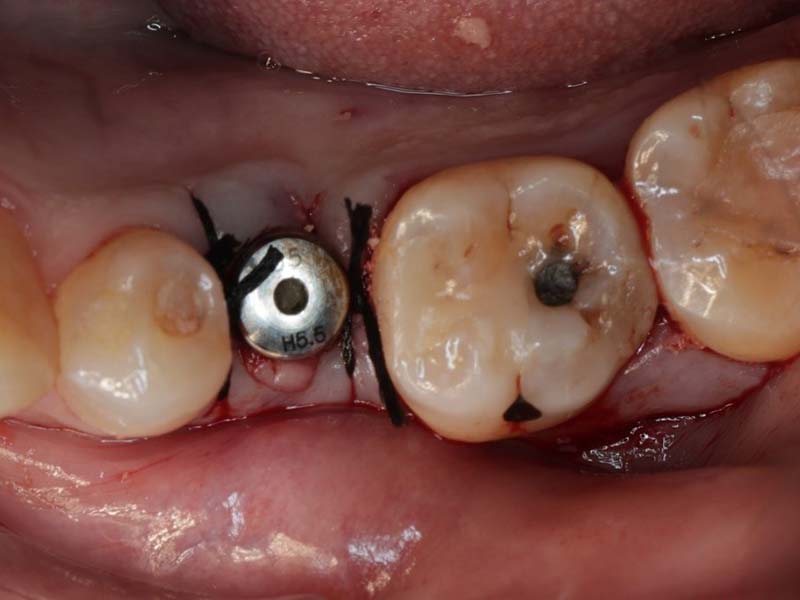

使用數位手術導板精確定位植體位置,確保角度與深度正確,提升植牙成功率

植牙案例分享